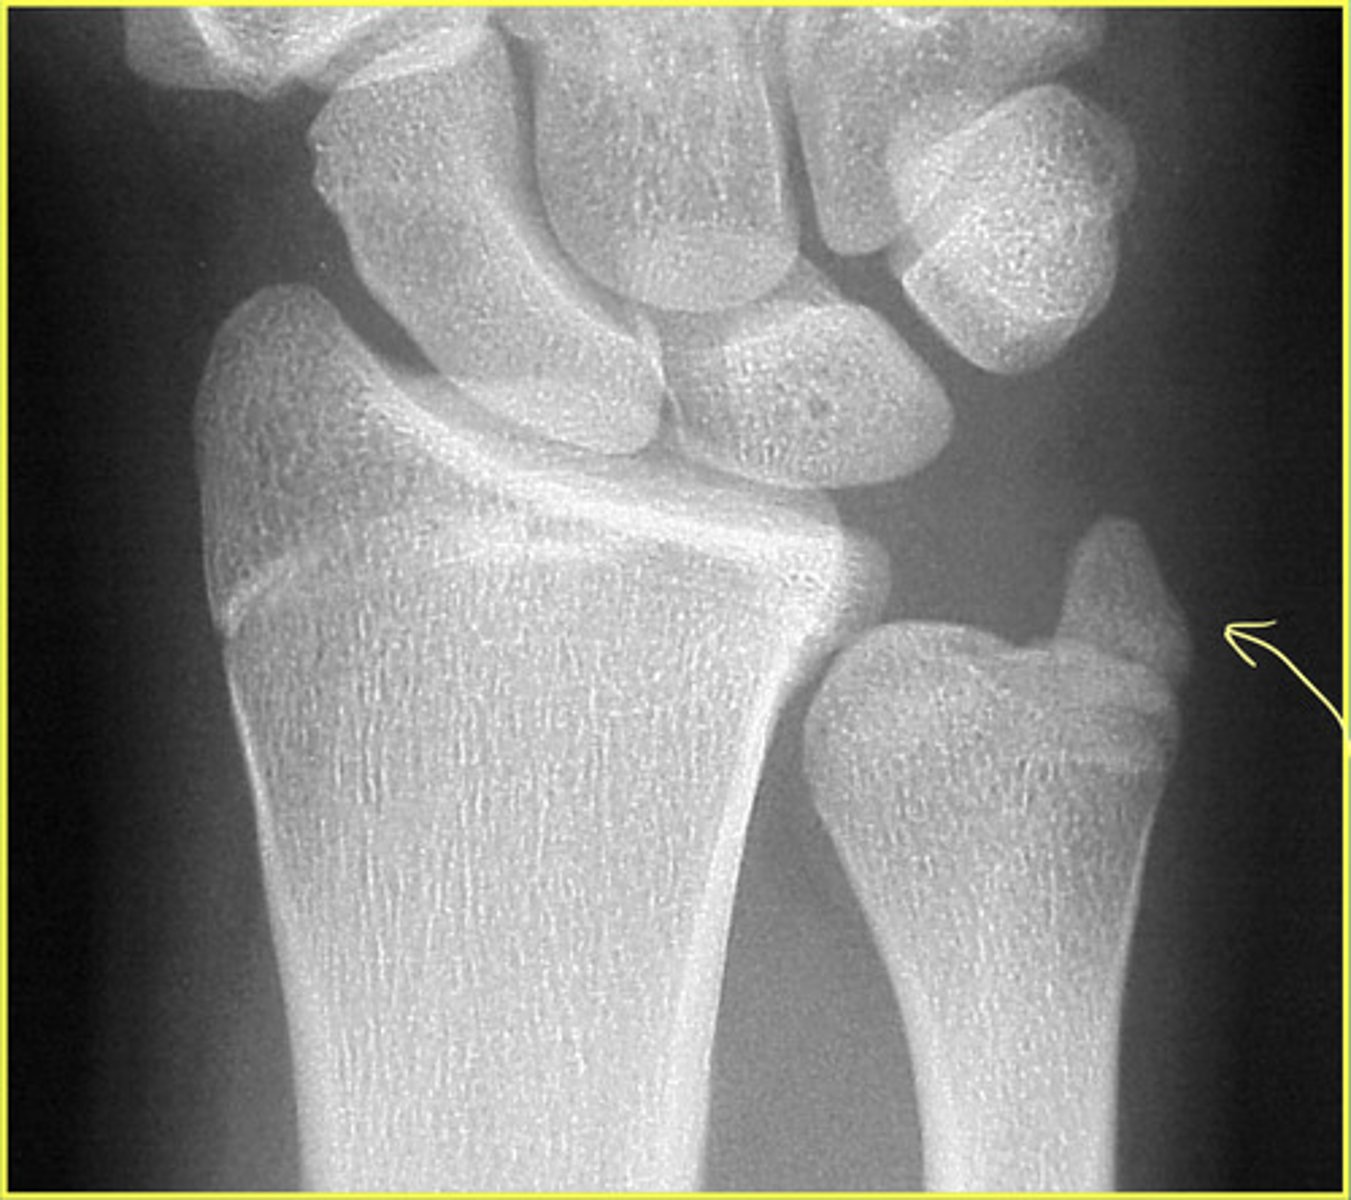

Negative Ulnar Variance

Relative shortness of the ulna compared to the radius

Measured by comparing the distal ends of each bone

What is the clinical significance of ulnar variance?

May lead to lunate avascular necrosis

Lunate avascular necrosis = Keinbock Disease

Positive Ulnar Variance

Relative lengthening of the ulna compared to the radius

Clinical significance of positive ulnar variance

May lead to ulnar abutment (impaction) of the lunate and TFCC (triangular fibrocartilage complex) degeneration

May be associated with triangular fibrocartilage tear

What is the measurement to consider positive or negative ulnar variance?

Positive = level of the ulna is > 2.5 mm beyond the radius margin

Negative = ulna is less than or equal to 2.5 mm than the radius margin